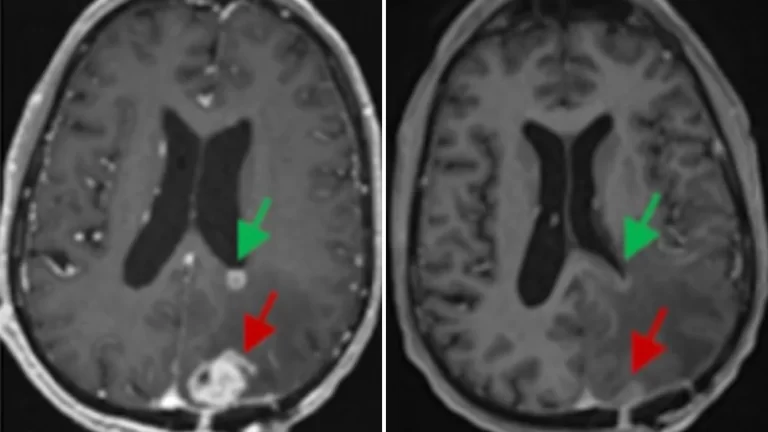

After a single 10-milliliter infusion of about 10 million CAR-T cells, Fraser’s tumor began to shrink. On an MRI scan the next day, it was nearly 20% smaller, and within weeks, it was barely detectable. He’s seen no progression of his cancer for about six months now, according to his doctors. He’s just had his third brain surgery.